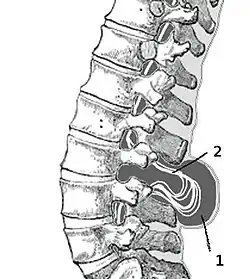

Spina bifida aperta (Миеломенингоцеле)

Эта наиболее тяжёлая форма составляет около 75 % всех форм расщепления позвоночника. Через дефект позвоночника выходит часть спинного мозга (так называемая мозговая грыжа). В некоторых случаях «мешочек» со спинным мозгом может быть покрыт кожей, в других случаях наружу могут выходить сама ткань мозга и нервные корешки. Степень неврологических нарушений напрямую связана с локализацией и тяжестью дефекта спинного мозга. При вовлечении в процесс конечного отдела спинного мозга могут отмечаться нарушения только мочевого пузыря и кишечника. Более тяжелые дефекты могут проявляться в виде параличей ног вместе с нарушением функции мочевого пузыря и кишечника.